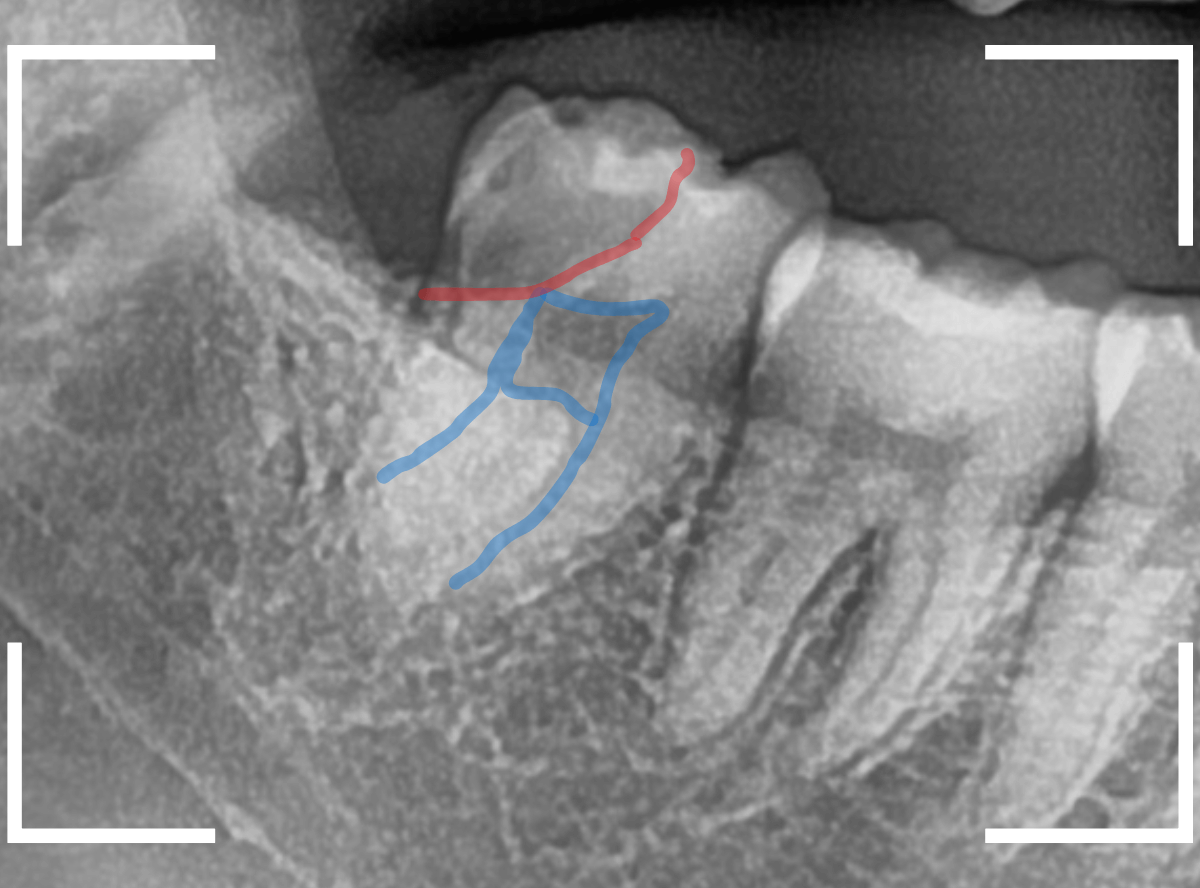

抜歯後に長期間お痛みが出たり、経過観察が必要な難しいおやしらずの抜歯ならまだしも、簡単なおやしらずの抜歯を避けてしまったがために、他の歯に悪影響を与えてしまったもったいない例も多々見てきました。

ここでは、比較的簡単なおやしらずの抜歯の例を中心にご紹介します。